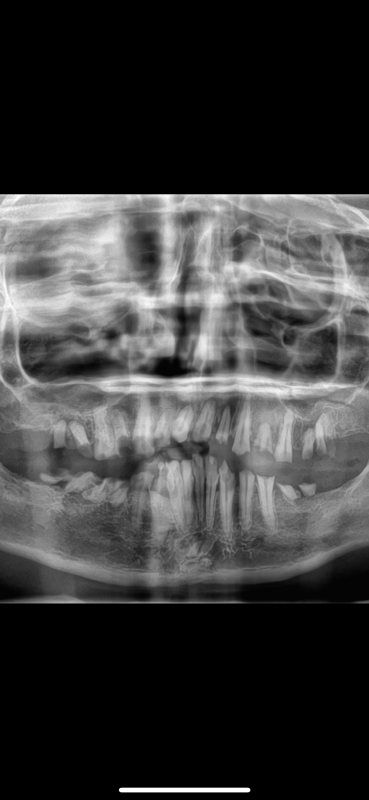

Hi, my name is Karen, and I’m reaching out with a humble heart to ask for your support. I’ve been struggling with serious dental issues that are affecting not only my health but also my confidence and ability to enjoy everyday life. After consulting with a dentist, I’ve learned that I need extensive dental work that goes beyond what I can afford right now.

The total cost includes surgical and non surgical removal of the teeth, anesthesia,  dentures and unfortunately, I don’t have dental insurance. This situation has made it hard to eat, speak, and smile without discomfort or embarrassment.